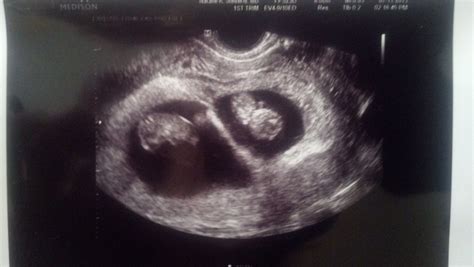

• Visualization of Embryos: At 7 weeks, the embryos are about the size of a blueberry. The ultrasound will show the gestational sacs, yolk sacs, and the fetal poles, which are the early forms of the embryos.

• Chorionicity and Amnionicity: The ultrasound can also help determine the type of twin pregnancy, whether it is dichorionic/diamniotic (fraternal twins with separate placentas and amniotic sacs) or monochorionic/diamniotic (identical twins sharing a placenta but with separate amniotic sacs).

• Gestational Sacs: The presence of gestational sacs confirms the implantation of the embryos in the uterus.

• Yolk Sacs: Yolk sacs are essential for the early development of the embryos and should be visible at this stage.

• Fetal Poles: Fetal poles are the early forms of the embryos and should be visible within the gestational sacs.

• Heartbeats: The detection of fetal heartbeats is a positive sign of a viable pregnancy, although it may not always be visible at 7 weeks.